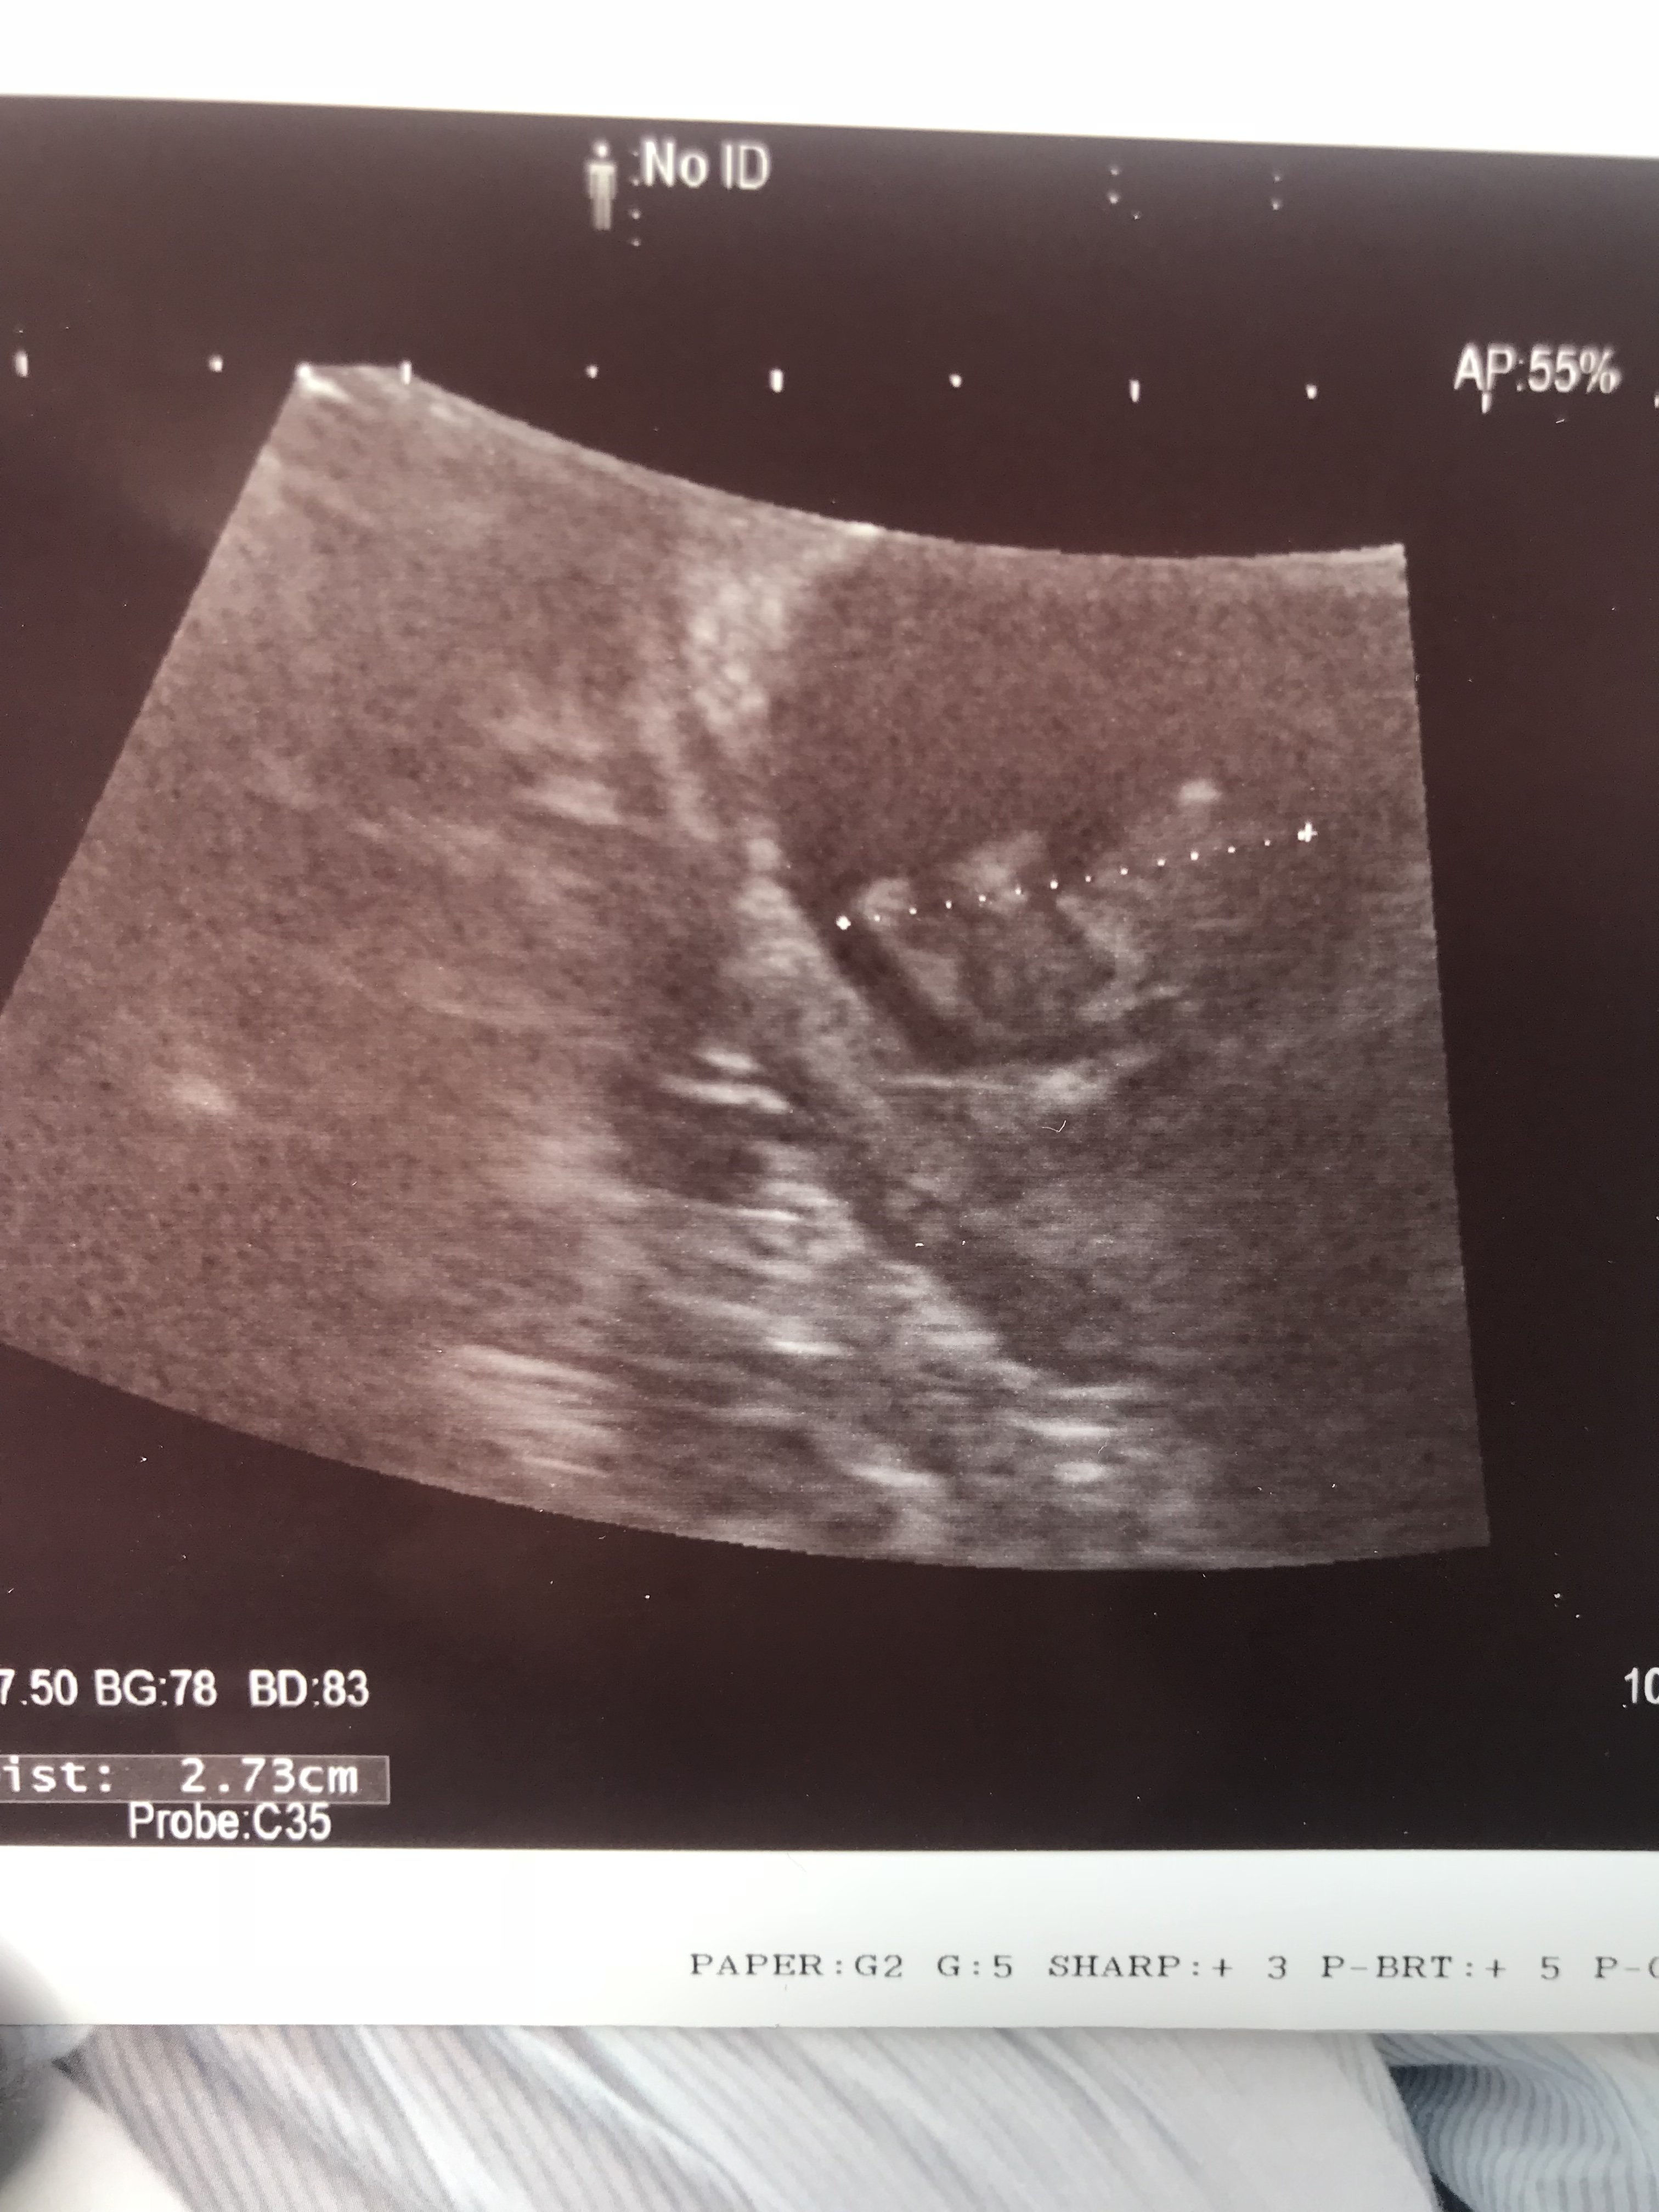

Nasz malutki człowieczek ;) 9tc+1 wszystko dobrze ;) zakrywal się rączka ;) moja miłość ,a ciśnienie mam mierzyć 3 razy dziennie i zapisywać ,odstawić całkowicie sól i tylko wodę pic i na następna wizytę ta kartkę przynieść ;) jestem szczęśliwa

Zobacz załącznik 894399 Nasz malutki człowieczek ;) 9tc+1 wszystko dobrze ;) zakrywal się rączka ;) moja miłość ,a ciśnienie mam mierzyć 3 razy dziennie i zapisywać ,odstawić całkowicie sól i tylko wodę pic i na następna wizytę ta kartkę przynieść ;) jestem szczęśliwa